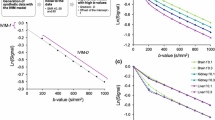

To determine whether a mono-, bi- or tri-exponential model best fits the intravoxel incoherent motion (IVIM) diffusion-weighted imaging (DWI) signal of normal livers.

The pilot and validation studies were conducted in 38 and 36 patients with normal livers, respectively. The DWI sequence was performed using single-shot echoplanar imaging with 11 (pilot study) and 16 (validation study) b values. In each study, data from all patients were used to model the IVIM signal of normal liver.

Diffusion coefficients (Di ± standard deviations) and their fractions (fi ± standard deviations) were determined from each model. The models were compared using the extra sum-of-squares test and information criteria.

The tri-exponential model provided a better fit than both the bi- and mono-exponential models. The tri-exponential IVIM model determined three diffusion compartments: a slow (D1 = 1.35 ± 0.03 × 10-3 mm2/s; f1 = 72.7 ± 0.9 %), a fast (D2 = 26.50 ± 2.49 × 10-3 mm2/s; f2 = 13.7 ± 0.6 %) and a very fast (D3 = 404.00 ± 43.7 × 10-3 mm2/s; f3 = 13.5 ± 0.8 %) diffusion compartment [results from the validation study]. The very fast compartment contributed to the IVIM signal only for b values ≤15 s/mm2

The tri-exponential model provided the best fit for IVIM signal decay in the liver over the 0-800 s/mm2 range. In IVIM analysis of normal liver, a third very fast (pseudo)diffusion component might be relevant.

• For normal liver, tri-exponential IVIM model might be superior to bi-exponential

• A very fast compartment (D = 404.00 ± 43.7 × 10 -3 mm2 /s; f = 13.5 ± 0.8 %) is determined from the tri-exponential model

• The compartment contributes to the IVIM signal only for b ≤ 15 s/mm 2